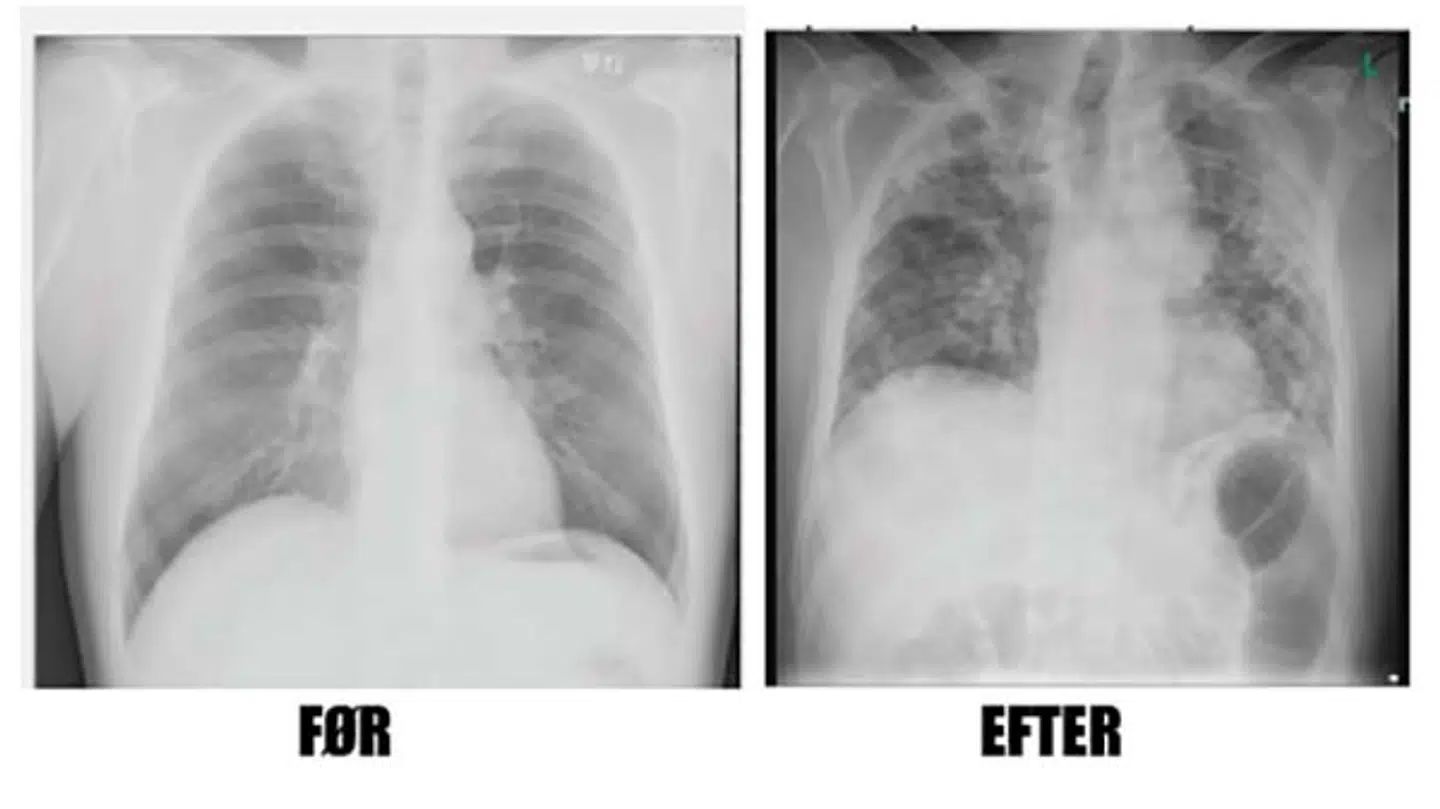

Her viser han bl.a. et før- og efterbillede af lungerne på midaldrende mand, som har været indlagt i over to uger på intensiv med coronavirus.

»Man kan jo godt være bekymret for følgevirkninger,« siger Toke Barfod om billederne, hvor det første er taget i 2014, mens det andet billede af lungerne med betydelige betændelsesforandringer er taget efter udskrivelsen fra intensiv, hvor manden altså er ovre virussen.